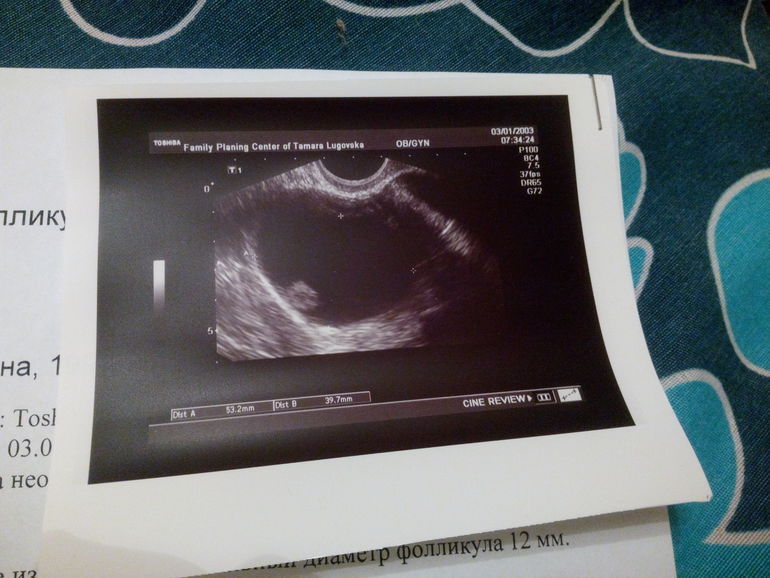

Девочки, у меня нет больше сил((( в том цикле была киста 31*28 мм. Врач сказала ничего не делать и ждать М. М пришли вовремя, без задержек . Решила отслеживать О по узи...Пошла сегодня, а тут такая картина!!!!!Еще и кровь на туалетной бумаге прямо перед узи обнаружила

получается киста увеличилась?

Ну да 😔я 11 месяцев назад перенесла операцию по разрыву кисты и катастрофически боюсь повторения!!!!!!! В сентябре тоже была киста таких размеров, врач выписала свечи, может, стоит их поставлять....

Щелково